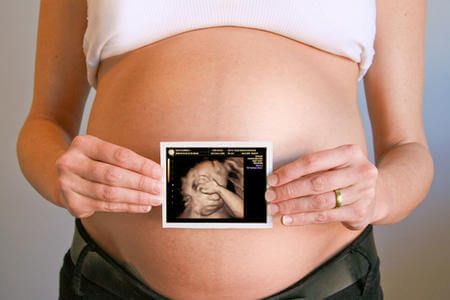

Während der Schwangerschaft bereitet sich dein Baby auf das Leben vor und tut dies durch die Botschaften, die du ihm als Mutter vermittelst, sagt Curt A. Sandman. Er ist einer der Wissenschaftler, die kürzlich an einer der Universität von Kalifornien-Irvine durchgeführten Studie teilgenommen haben. Die Studie beweist, dass die Veränderung des Geisteszustands der Mutter die Entwicklung ihres Babys vor und nach der Geburt beeinflusst.